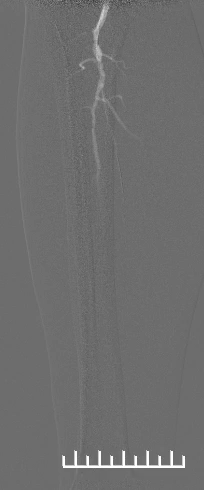

1.造影评估:左股动脉翻山入路,经鞘管造影见右股浅动脉中下段局限重度狭窄,远端股腘动脉、膝下动脉延迟显影,血流流速缓慢(图2,3,4)。

(图2)

(图3)

(图4)